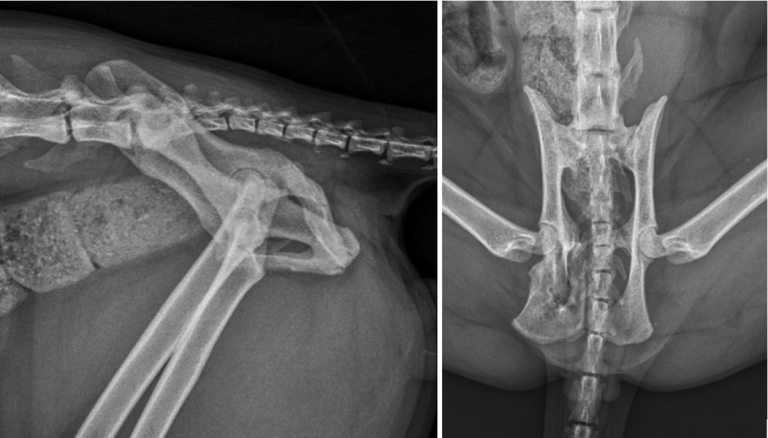

Figure 2. Lateral and ventrodorsal radiographic projections of the pelvis demonstrating malunion of the right ischium and pubis.

Radiography of the abdomen (Figure 1) revealed a full and severely distended colon. The seventh lumbar vertebra measured 17mm and the colon at its widest part measured 30mm, confirming megacolon. Views of the pelvis (Figure 2) revealed deformities consistent with malunion of the right ischium caudal to the acetabulum and of the pubis on the right side. The sacral index measured 71%, suggesting a low risk of constipation.